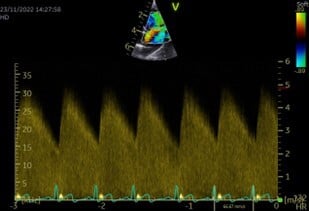

Due to its characteristic murmur, the index of suspicion for an uncomplicated (“left-to-right”) PDA may be high from physical exam findings alone; however, a definitive diagnosis requires echocardiography. The ductus can typically be visualised entering the pulmonary artery (Figure 1), and continuous flow through the duct is apparent on spectral Doppler imaging (Figure 2). Left-sided cardiomegaly may also be apparent.